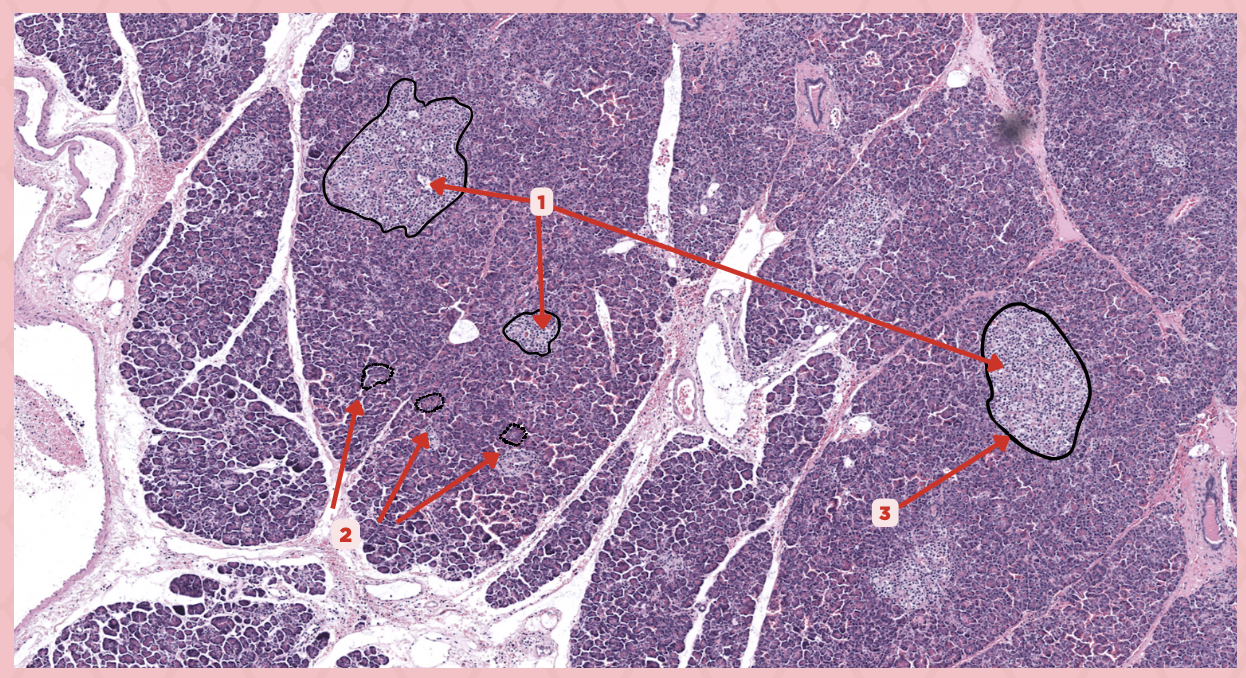

Pancreas

Identify the specimen.

Islets of Langerhans

Identify the structure labeled as 1.

Pancreatic Acini

Identify the structure labeled as 2.

Reticular Tissue

Identify the structure labeled as 3.

Beta-cells

Which cells occupy the central area of #1?

Pancreatic Acini

#3 delineates the pale- staining cells from the darker-staining cells. What do you call the darker-staining cells?